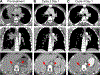

Results: Tarloxotinib-E inhibited cell signaling and proliferation in patient-derived cancer models in vitro by directly inhibiting phosphorylation and activation of EGFR, HER2, and HER2/HER3 heterodimers. In vivo, tarloxotinib induced tumor regression or growth inhibition in multiple murine xenograft models V体育ios版. Pharmacokinetic analysis confirmed markedly higher levels of tarloxotinib-E in tumor tissue than plasma or skin. Finally, a patient with lung adenocarcinoma harboring an ERBB2 exon 20 p. A775_G776insYVMA mutation demonstrated a dramatic clinical response to tarloxotinib. .